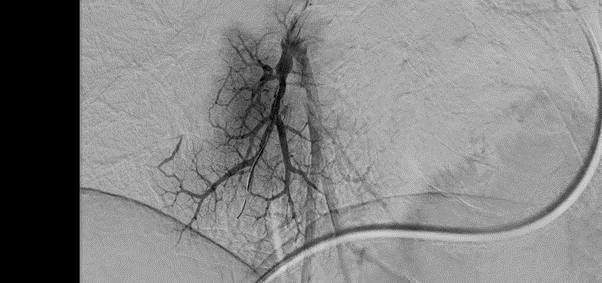

- Ангиография нижних конечностей

Картирование кровотока в ногах при диабете или атеросклерозе для планирования операции по восстановлению проходимости.

- Сосудистая диагностика и хирургия: лечение атеросклероза артерий ног

При атеросклерозе холестериновые бляшки нарастают внутри артерий ног, подобно накипи в трубах. Постепенно просвет сужается или закупоривается полностью. Кровь перестает поступать к стопе, ткани начинают отмирать — развивается гангрена. Раньше единственным выходом была ампутация. Баллонная ангиопластика (процедура, во время которой в область сужения вводят и раздувают под давлением баллонный катетер, расширяя таким образом кровеносный сосуд) позволяет сохранить конечность.

Позволяет получить идеально четкую картинку сосудов без помех от костей. Процесс происходит автоматически за доли секунды. Аппарат делает снимок до введения контраста, затем серию снимков с контрастом. Первое изображение компьютер накладывает на снимки с контрастом и убирает все, что совпало. Кости черепа, ребра или позвоночник полностью исчезают с экрана. Хирург видит только четкое дерево кровеносных сосудов на пустом фоне. Это позволяет заметить мельчайшие тромбы, аневризмы или сужения размером менее миллиметра.